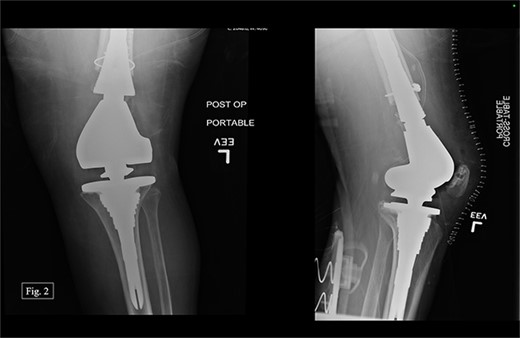

The previous medial parapatellar approach was used to identify and shell out the fractured DF with an arthroplasty component end block. Press fit trials were used, and the contralateral knee joint height was compared. We used the DePuy Synthes MBT revision metaphyseal sleeve, tibial tray rotating platform, MBT revision cemented, limb preservation system (LPS) tibial insert hinge, LPS distal femoral component, LPS sleeve adapter to distal femoral component, universal femoral sleeve, and a universal fluted stem. The patient experienced 1000 mL of intraoperative blood loss, awoke without incident, and was admitted to the ICU for monitoring and management. Postoperative anterior–posterior (AP) and lateral X-rays were taken (Fig. 2).

After being discharged from the University Medical Center, the patient visited Texas Tech Orthopedic Clinic 2 weeks after the operation. In July 2020, around 5 months after the operation, she stated that she was regularly and consistently doing physical therapy and reported a pain score of 4/10. During the visit, APand lateral left knee X-rays were taken (Fig. 3).